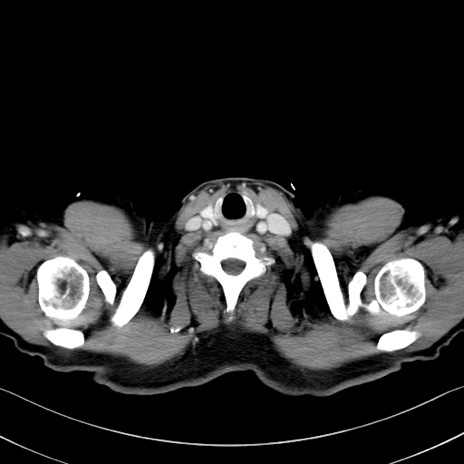

冠状断像

症例35(横断像)

【症例】70歳代 男性

【主訴】腹部膨満、嘔吐

【現病歴】昨日より腹部膨満感出現。本日増悪し、仙痛出現。嘔吐あり、受診。

【既往歴】糖尿病、胆摘後

【身体所見】BP 149/80mmHg、HR 74/min、BT 35.9℃、腹部:膨満、軟、圧痛なし。腸雑音減弱あり。上腹部正中切開瘢痕あり。

【データ】WBC 13500、CRP 1.72